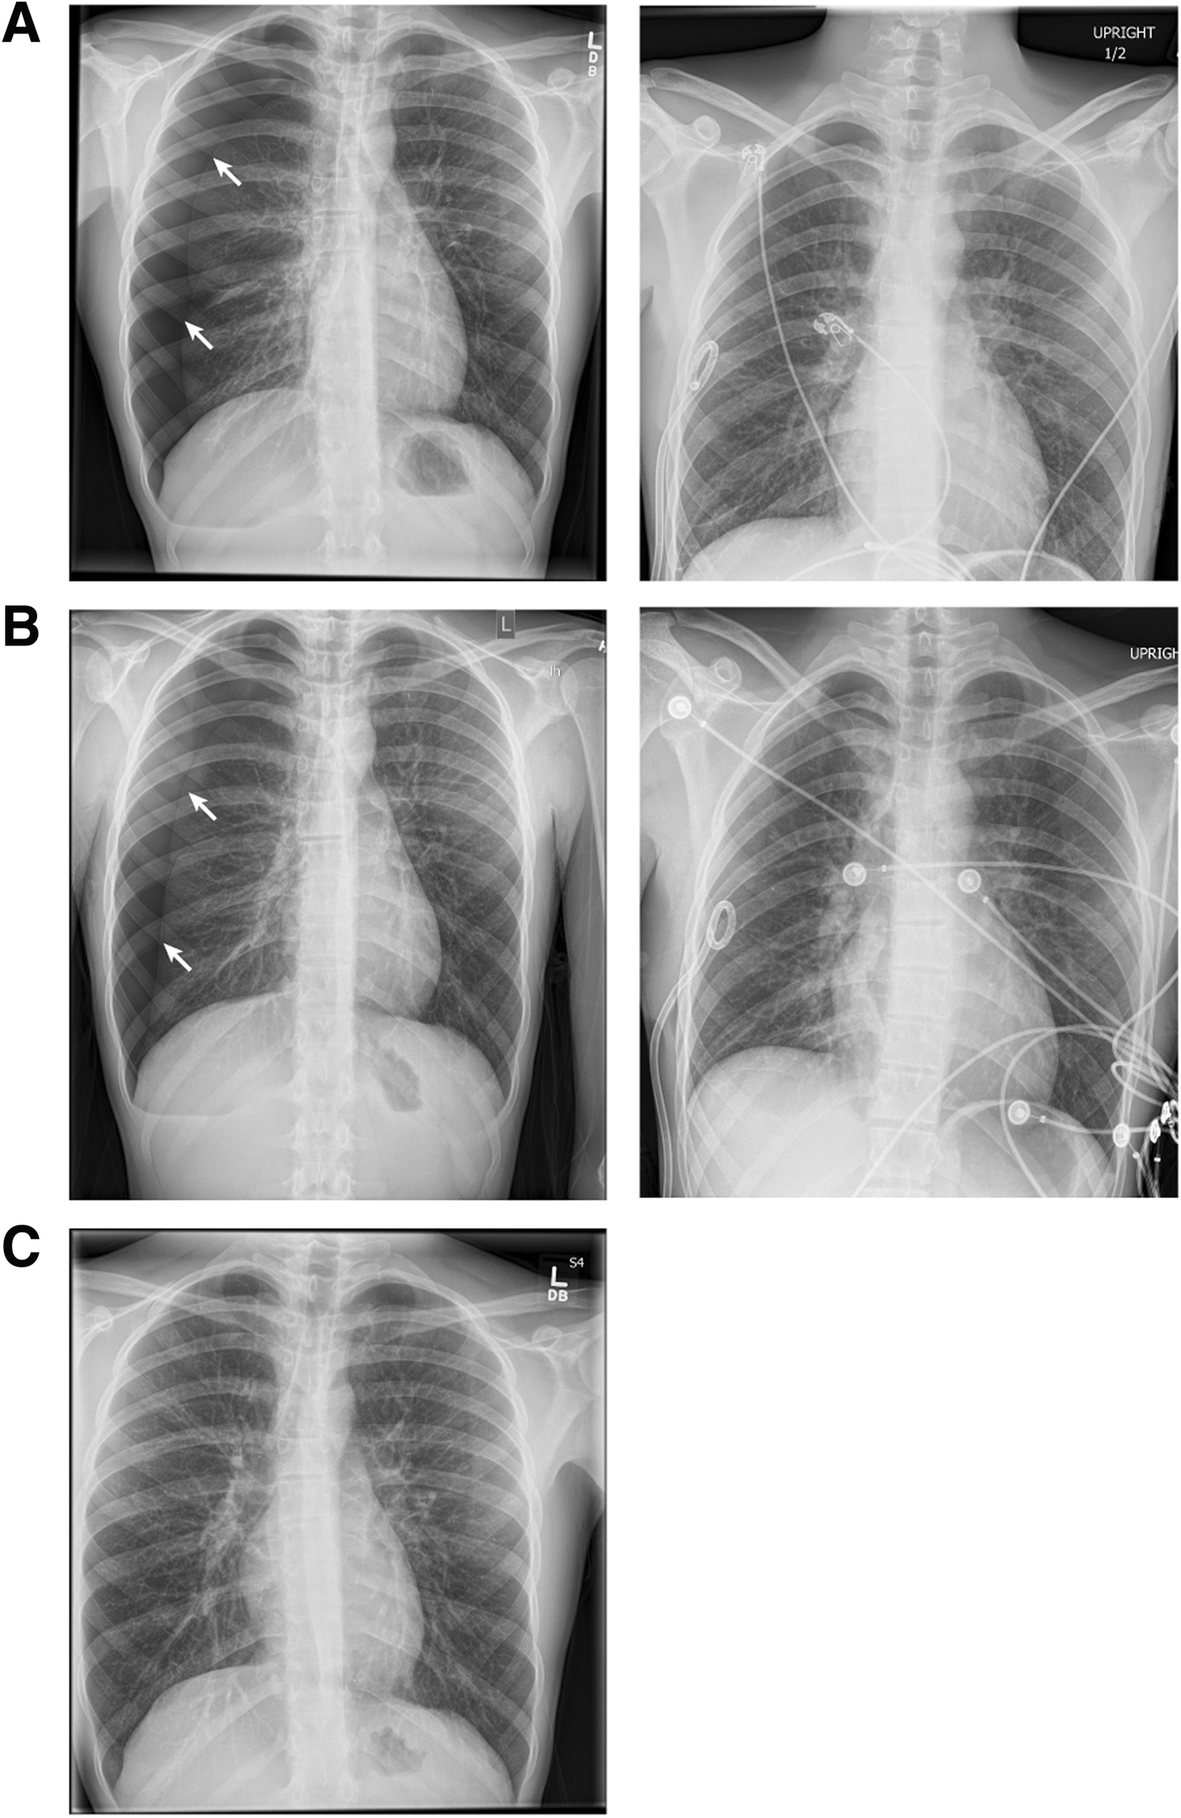

CXR Pattern Examples (Quick Look)

Pneumothorax on CXRWikimedia Commons

Pleural effusion on CXRWikimedia Commons

Lobar pneumonia on CXRWikimedia Commons

ARDS on CXRWikimedia Commons

Atelectasis on CXRWikimedia Commons